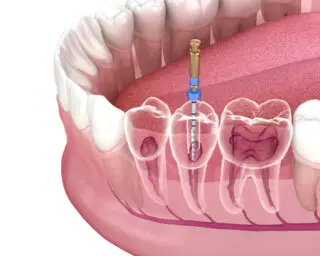

What happens in a root canal treatment?

Since the problem is deep-rooted, the procedure includes bacteria and decay extraction from the roots, nerve, and pulp. The procedure begins by disinfecting the area with antibiotics, followed by filling the empty roots and finally sealing the treated area from the tooth decay from erupting again.